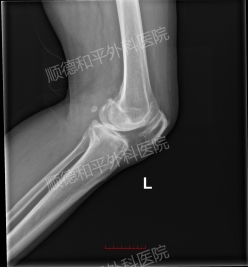

2个月前的意外扭伤,成为病情加重的“导火索”——左膝疼痛加剧,蹲下乏力、上下楼梯困难,日常简单动作都成了负担。门诊DR检查显示,她的左膝关节已出现退行性变、内侧关节间隙变窄,甚至伴随左膝轻度内翻、左下肢较右下肢短约7mm,保守治疗已无法阻止病情进展,也难以改善日益恶化的生活质量,这是她选择手术的核心原因。

精准解决病灶,恢复关节功能:手术无需切除整个膝关节,仅对受损的股骨髁、胫骨平台表面进行处理,通过植入4号股骨髁假体、4号胫骨平台假体与6mm厚胫骨垫片,重建关节结构。术中通过骨水泥固定假体,确保假体与骨界面紧密贴合,术后C臂机透视显示假体位置满意,膝关节稳定性与活动度均恢复良好,从根本上解决关节疼痛与活动受限问题。